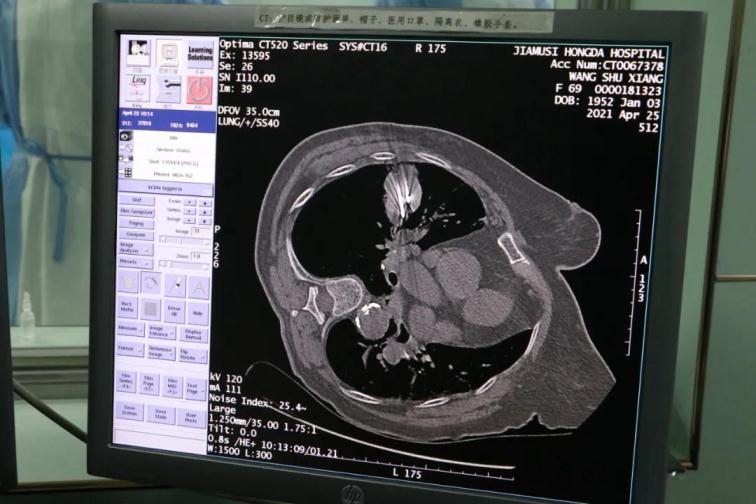

為了提高CT影像下肺腫瘤定位的精準(zhǔn)度,術(shù)前胸外科團隊聯(lián)合CT影像科趙文禮主任和董明鑫醫(yī)師詳細(xì)研究了肺CT定位方案,采取國際上先進的CT網(wǎng)格定位法,對肺腫瘤精確定位,定位精度可達(dá)5mm以內(nèi)。經(jīng)過團隊合作充分準(zhǔn)備后對肺癌實施了氬氦刀穿刺治療,微創(chuàng)穿刺針孔3mm,局麻鎮(zhèn)痛,分段治療40分鐘。病人全程在韋文康護士長護理團隊心肺監(jiān)測下進行,確保了手術(shù)安全。

氬氦刀治療后即刻CT評價肺腫瘤核心密度下降,手術(shù)后5天CT評價肺癌與周圍正常肺組織對比,水腫帶形成,癌組織出現(xiàn)壞死。治療取得了良好效果。遠(yuǎn)期效果需要繼續(xù)隨訪觀察。病人手術(shù)后1周無并發(fā)癥痊愈出院。